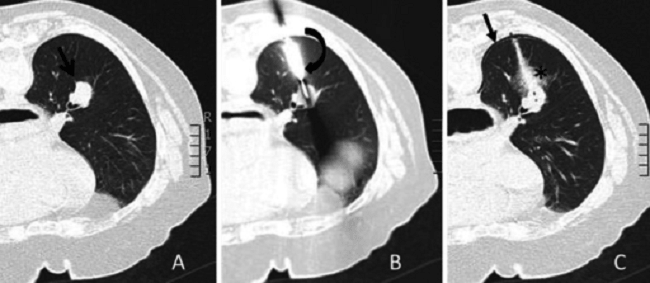

Transthoracic needle aspiration (TTNA) adalah tindakan biopsi jaringan paru dan organ di sekitarnya, yang biasa dilakukan untuk diagnosis kanker paru, lesi pleura, dan tumor mediastinum. Tindakan ini bersifat aman, cepat, dan efektif untuk menentukan berbagai jenis penyakit paru, terutama keganasan. Prosedur biopsi melalui TTNA menjadi lebih akurat dan efisien karena telah disertai dengan peningkatan teknologi pencitraan dan teknik sitopatologi.

Sumber Gambar: Openi, 2015.

Mayoritas prosedur TTNA dilakukan pada pasien rawat jalan dengan menggunakan anestesi lokal, dengan atau tanpa sedasi. Tindakan ini disarankan untuk dituntun oleh USG toraks atau CT scan toraks, untuk mengurangi risiko komplikasi. Contoh komplikasi yang bisa muncul karena TTNA adalah pneumothorax, perdarahan, hemoptisis, dan emboli udara. TTNA juga berpotensi menyebabkan tumor seeding.[1-7]